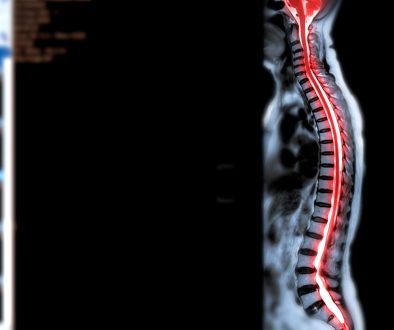

1. **الفحوصات الطبية**:

تأكد من إجراء جميع الفحوصات اللازمة مثل الرنين المغناطيسي أو الأشعة المقطعية.